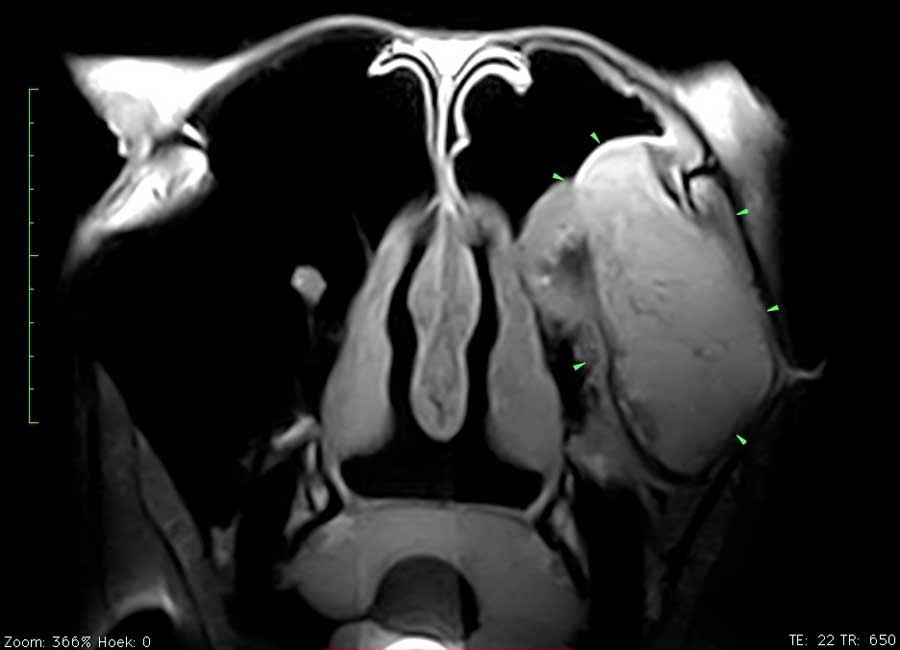

Dit paard had sinds enkele weken een unilaterale bloederige neusvloei. Op endoscopisch onderzoek was slechts een minimale afwijking ter hoogte van het linker ethmoid te zien. Bij radiografisch onderzoek was een grote massa in de sinus te zien. Er werd beslist een pre-operatieve MRI uit te voeren om de operatie te plannen en ook prognose beter te kunnen inschatten. Het ethmoid hematoom (PEH) bleek een groot deel van de linker sinus ingenomen te hebben.